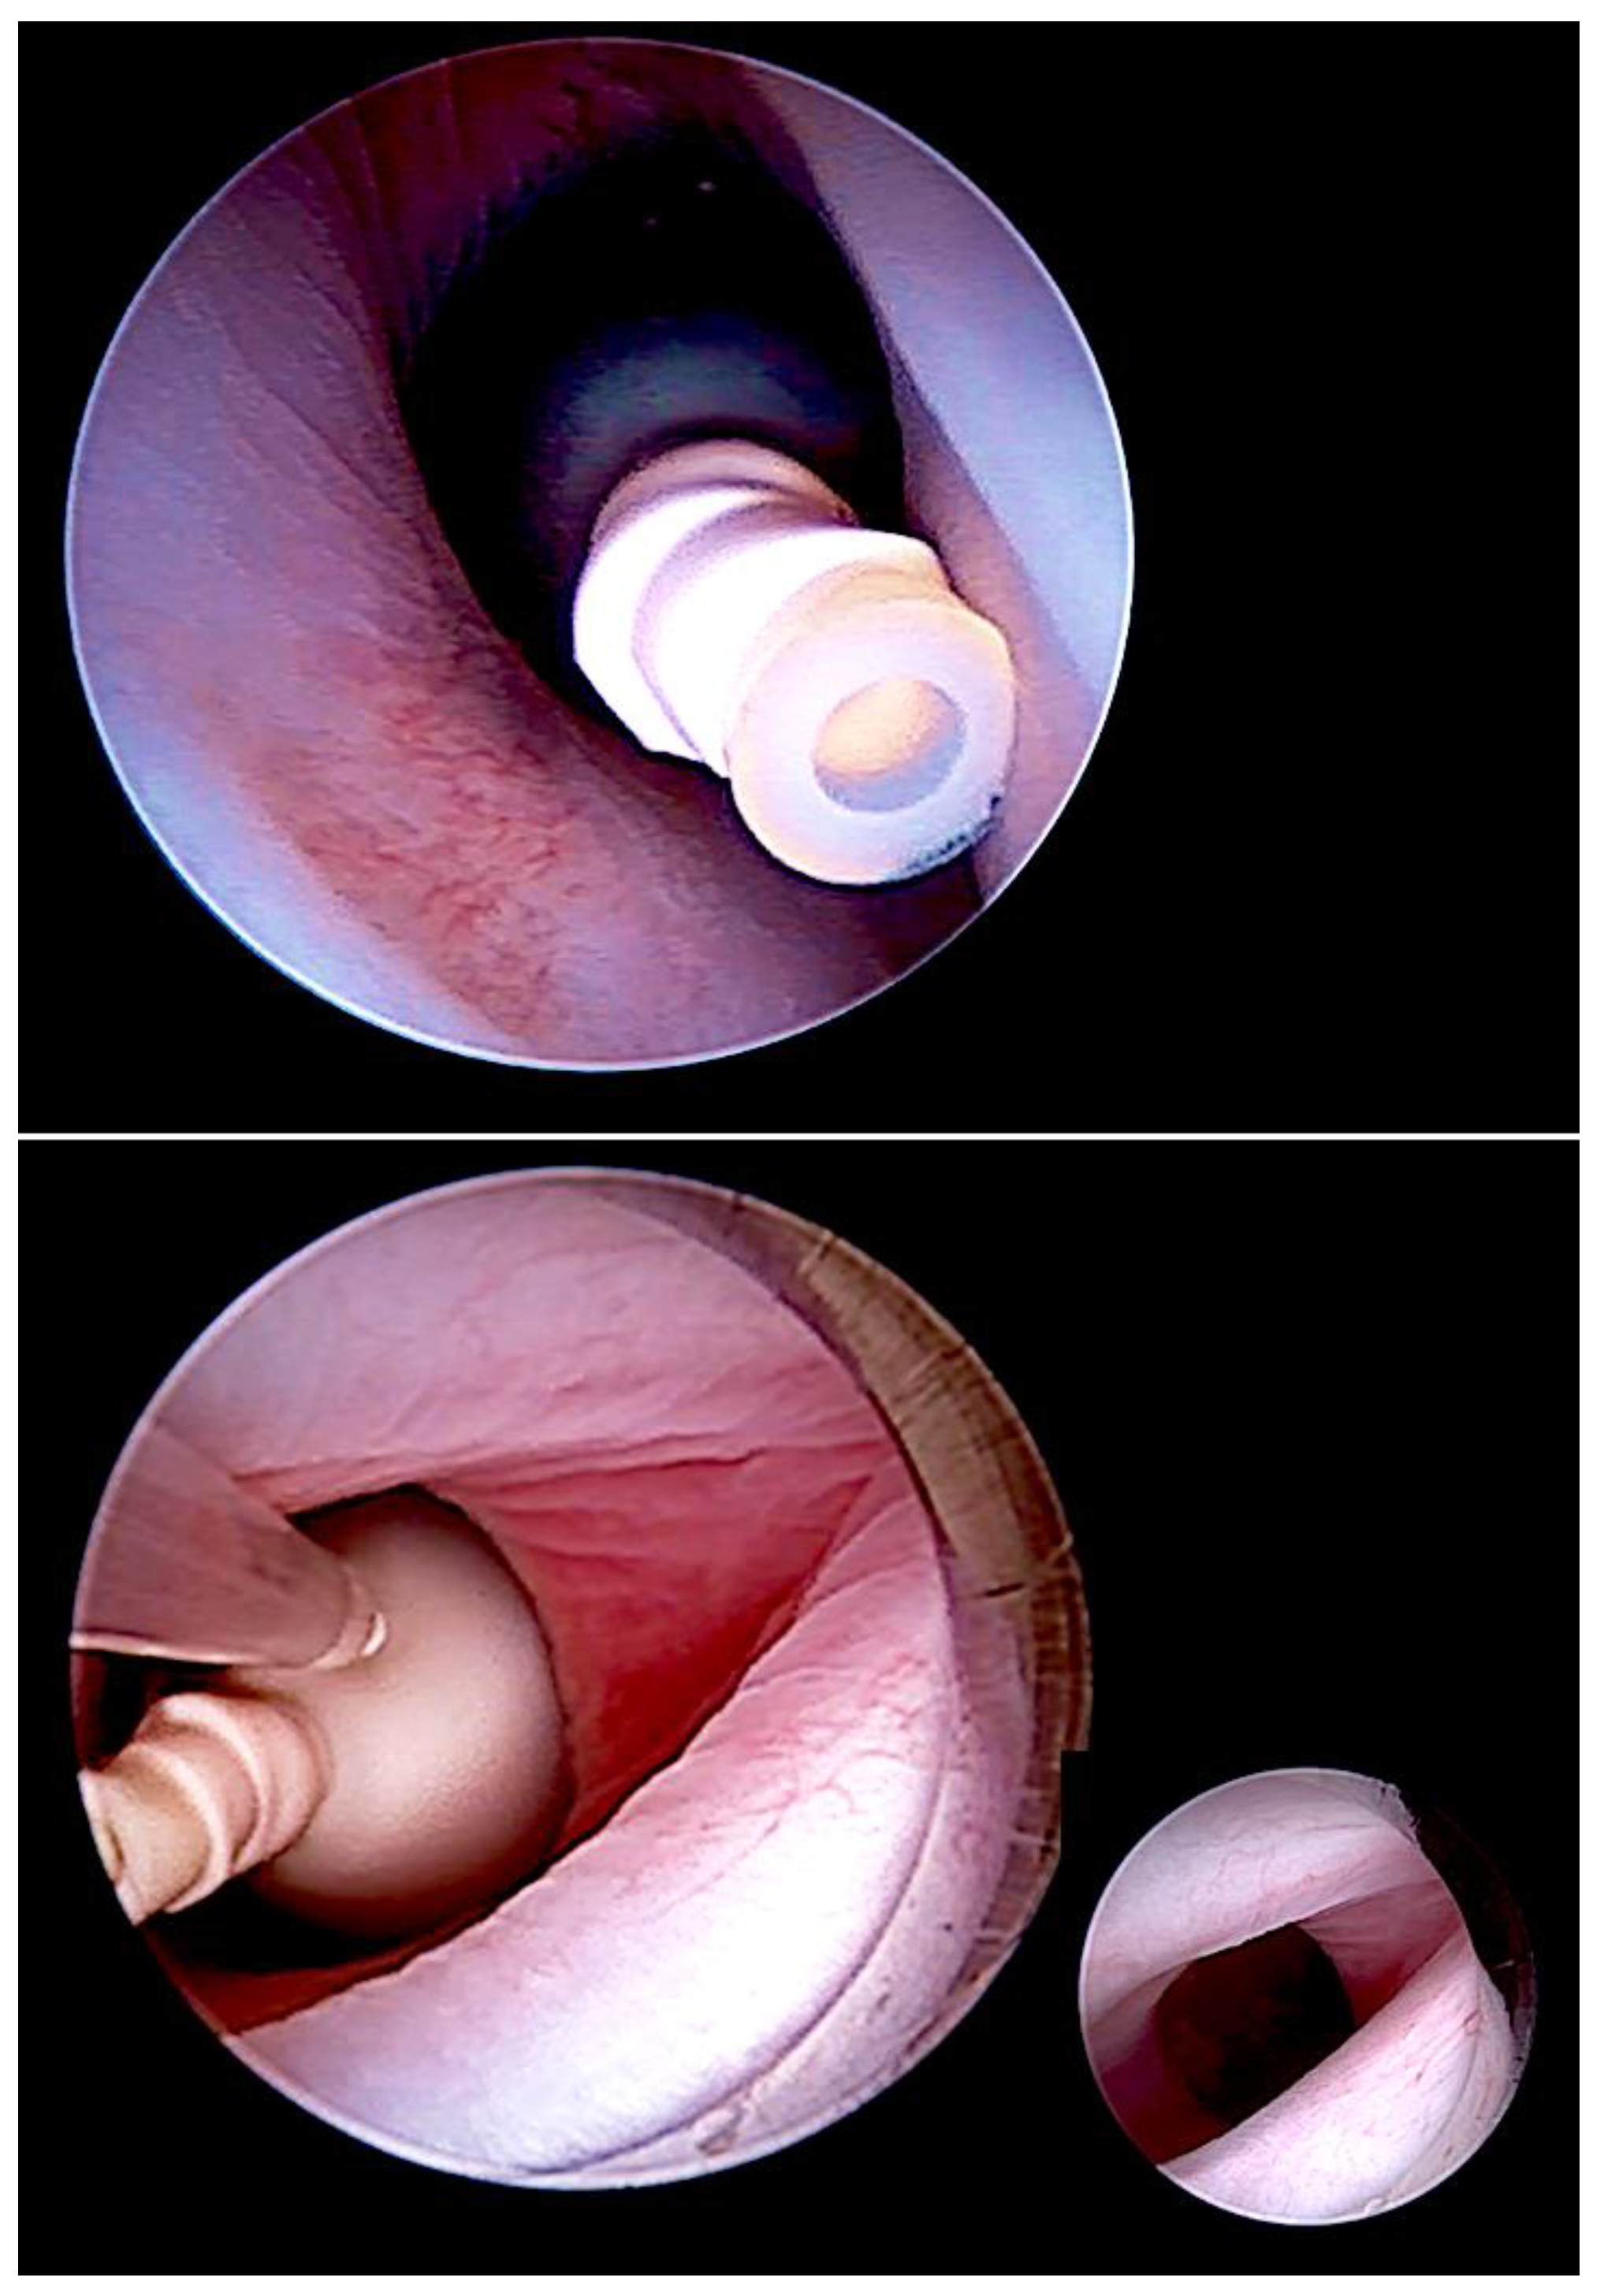

In contrast, during our minimally invasive fetoscopic approach, the spinal tissue is carefully dissected from the surrounding structures and then simply covered water-tightly by a patch [83]. The patch is trimmed in such a fashion that it permits sufficient accumulation of cerebrospinal fluid between the neural tissue and the inner patch surface, decreasing the risk of adhesions and avoiding compression (Figure 9). In their assessment of the effect of open fetal surgery and minimally invasive fetoscopic surgery for spina bifida on neuromuscular outcomes, Verbeek and colleague observed in a small series of fetuses that segmental neuroprotection (sensory and motor function) was better preserved by fetoscopy than open fetal surgery (fetoscopy: +2 segments (−1.5–5) versus open: +0.25 segments (−2.5–6), respectively); (p = 0.04) [99].

Figure 9.

Top left—fetoscopic aspect of a flat myelomeningocele at the L4 level at 25 weeks of gestation after successful fetal posturing in the carbon dioxide-insufflated amniotic cavity. Top right—at first, the lesion is circumcised, then, the placode (P) and spinal nerves are carefully dissected from surrounding structures (middle left and right). The neural tissue is then covered water-tightly by a patch (bottom left). The patch has been trimmed in such a fashion that it permits sufficient accumulation of cerebrospinal fluid (CF) between the placode (P arrow) and the inner patch surface, greatly decreasing the risk for adhesions and avoiding compression (bottom right).